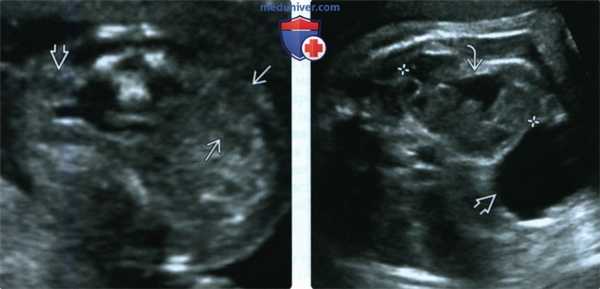

(Слева) УЗИ плода в 19 нед., поперечный срез через почечные ложа. Единственная почка. Петли кишечника, заполняющие противоположное почечное ложе, можно ошибочно принять за почку. Пустое почечное ложе -первый признак эктопии почки; на ранних сроках беременности эктопическую почку трудно обнаружить.

(Справа) Эктопия почки может сочетаться с аномалиями почки. В данном случае имеется незначительная пиелэктазия и незавершенный поворот почки. Почечная лоханка ориентирована кпереди и вбок (мочевой пузырь).